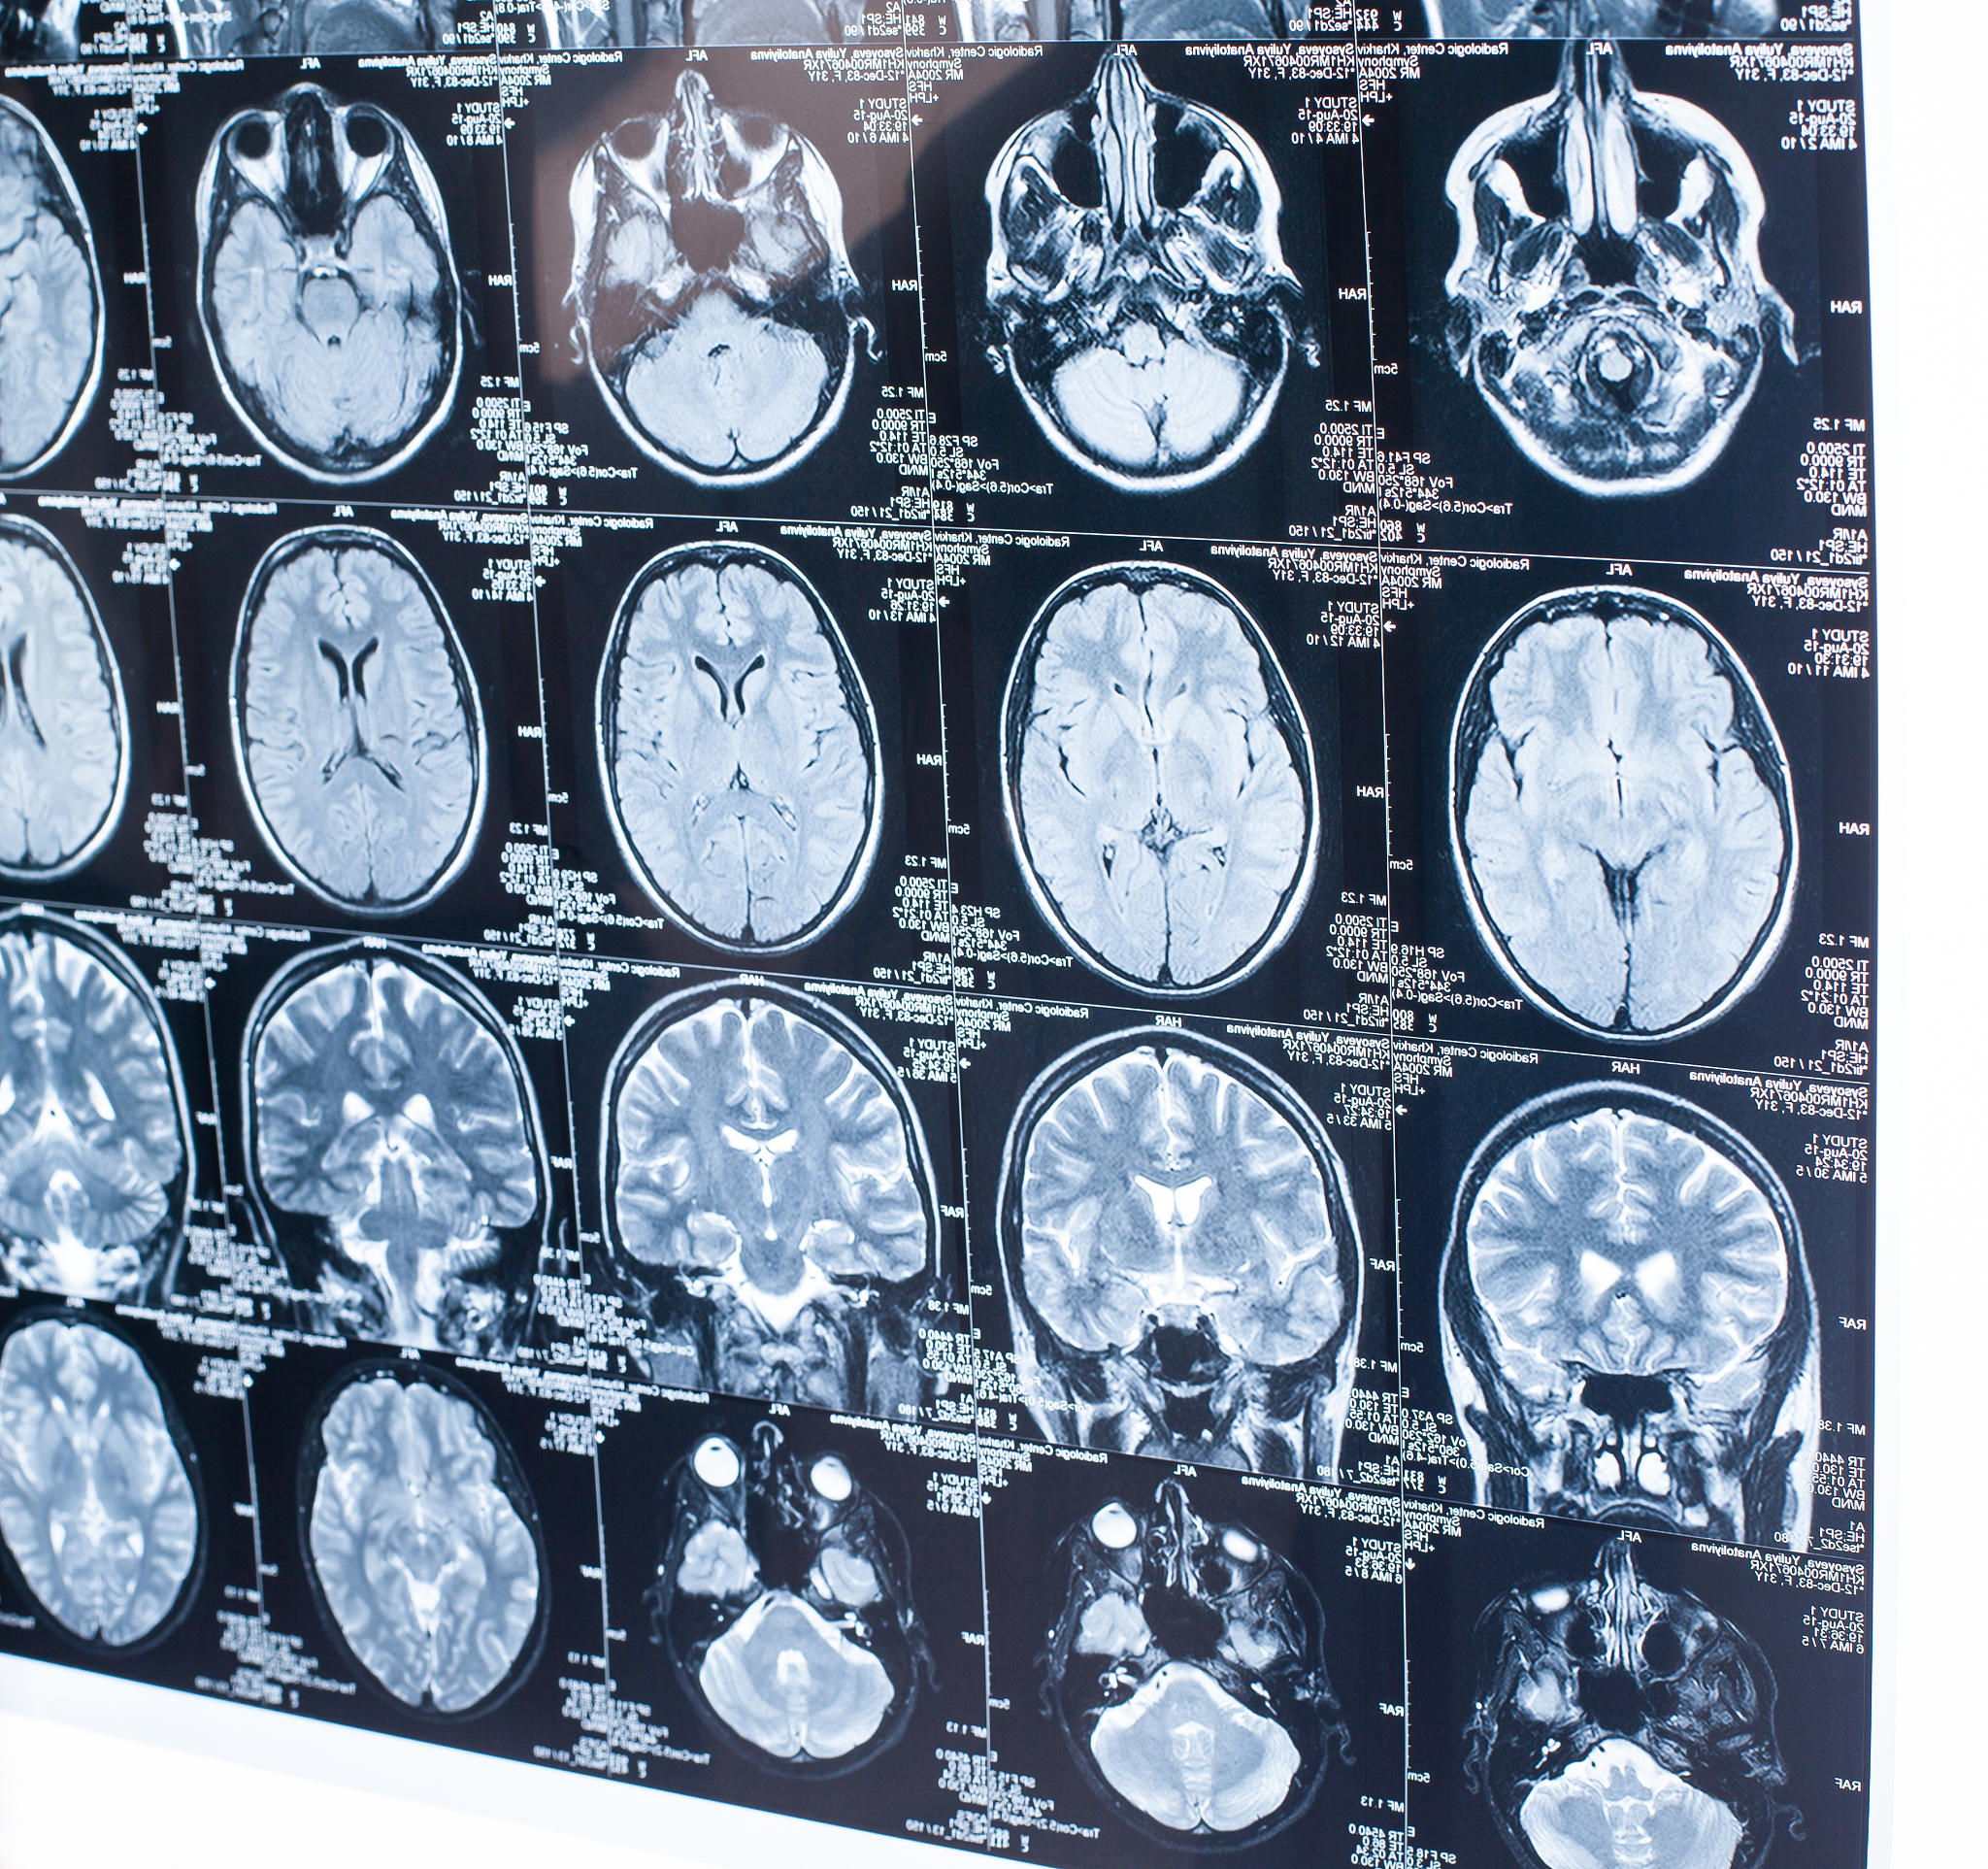

婴儿头颅MRI检查结果分析:髓鞘化进程正常,左侧颞部脑外间隙稍宽

此次头颅MRI检查结果显示脑皮髓质分界清晰,脑实质未见异常,脑室大小和形态正常,脑沟和脑裂未见异常,中线结构未见移位。符合髓鞘化进程。左侧颞部脑外间隙稍宽,建议随诊观察。